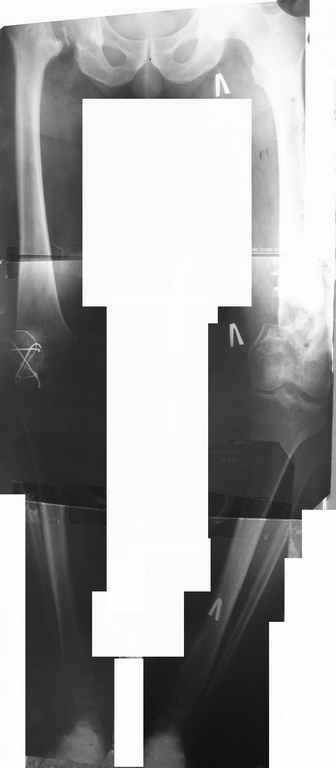

Был оперирован, среди прочего - остеосинтез DHS-фиксатором чреcшеечного перелома правого бедра, DCS-фиксатором остеосинтез оскольчатого чрезмыщелкового перелома левого бедра. Однако, в связи с развитием гнойного коксита были вынуждены убрать DHS-фиксатор и головку. Гнойный свищ правого тазобедренного сустава закрылся сразу после операции. Из-за вторичного смещения и поломки винтов пришлось удалить DCS-фиксатор и сращивать левое бедро внешней иммобилизацией. Прошло чуть более года. Пациент ходит с опорой на обе ноги,пользуется палочкой. Справа относительное укорочение 3см. Слева варус 33гр., тугой ложный сустав н/3бедра. Движения в коленных суставах почти в полном объёме.Перед нами встали вопросы, с чего начать? Протезирование правого ТБС? Восстановление опорности левой конечности? Воспользоваться-ли для этого интрамдулярным остеосинтезом гвоздём с блокированием с ретроградным введением? Стараться при этом восстановить полностью длину, или оставить на потом, на аппаратное решение? Или сразу попытаться использовать аппарат Илизарова? Но боимся потерять колено? Вопросов много.С благодарностью выслушаем все мнения.Заранее спасибоРахматуллин Ринат НургаяновичГКБ N 13 г.Уфа.